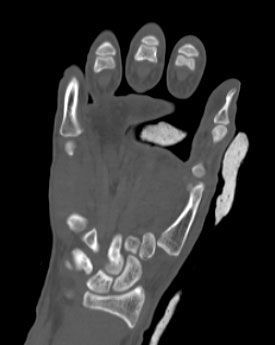

Κατάγματα Άνω Άκρων

Ορισμένες από τις περιπτώσεις καταγμάτων Άνω Άκρων που έχει αντιμετωπίσει ο κ. Παπασωτηρίου Αντώνιος.